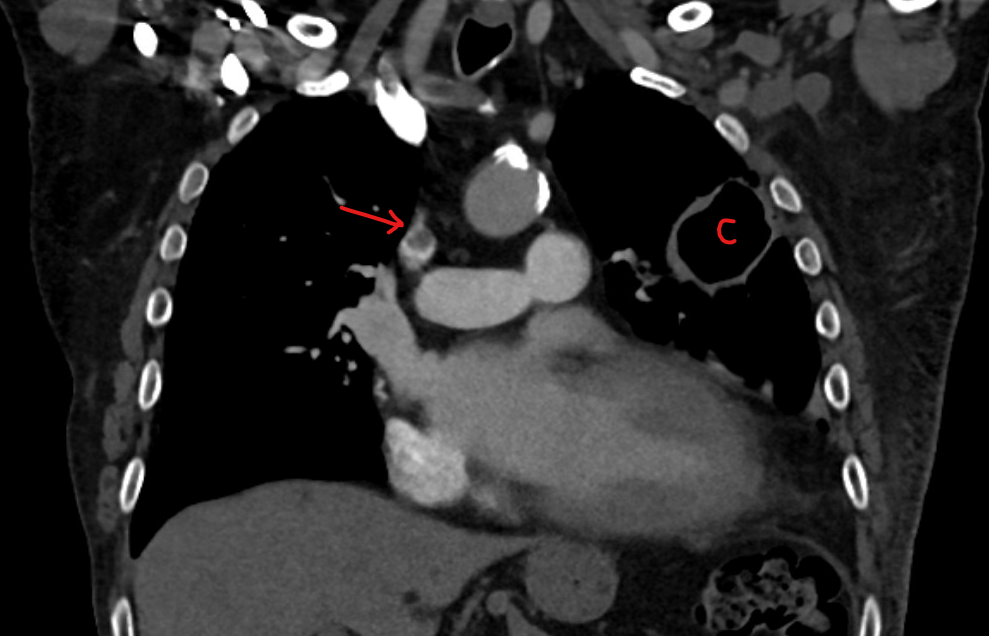

The diagnosis of venous and arterial thrombosis in cancer patients is similar to any other patient. Perhaps one difference is that cancer patients tend to have imaging studies for the cancer. So sometimes clots are discovered incidentally. A common example is an incidental findings of a pulmonary embolism on a staging chest CT.

Ultrasound is the most common test to use to visualize and prove a deep vein thrombosis. CT of the chest is the most common scan to prove a pulmonary embolism. A V/Q scan is also possible.